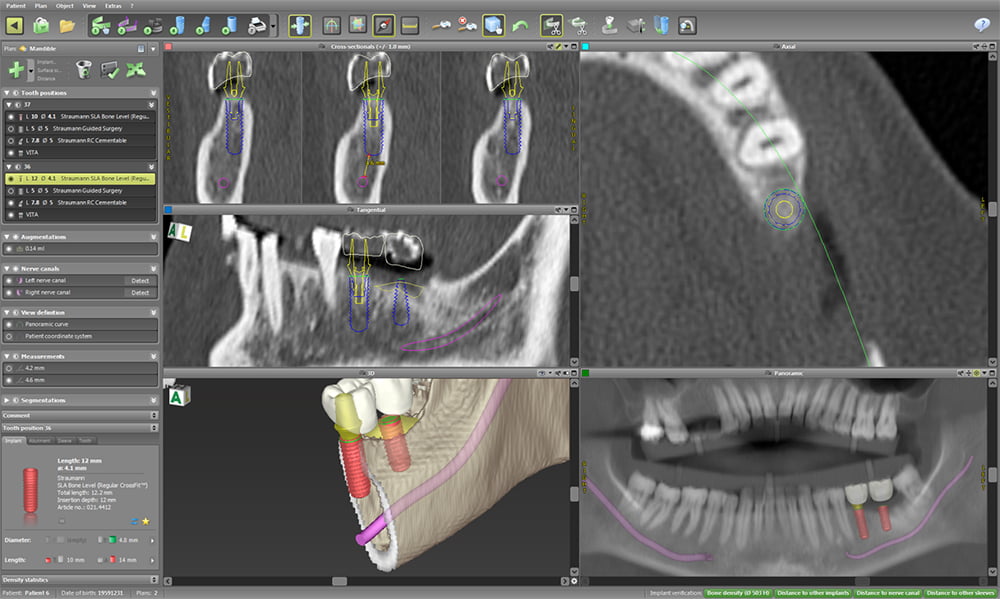

インプラント治療を行う上で最も大切なこと、それは「診断」です。CTやシュミレーションソフトを用いて事前に「骨の形態」「血管の位置」などを正確に把握し、適切な診査・診断を行うことで、安心安全なインプラント埋入位置を正確に決定することが出来ます。このようにインプラントによって出来上がる歯の位置を中心に治療計画を立てて治療を進めることを "トップダウントリートメント" といいます。

長期的予後の良いインプラント治療を行うためには、トップダウントリートメントによりその部位に正確にインプラントを入れる必要があります。

お口・あご・お身体の状態を確認、把握し、安全に治療を行うために、レントゲンや口腔内の撮影、血液検査など、高性能な設備を使用して精密な検査を行います。